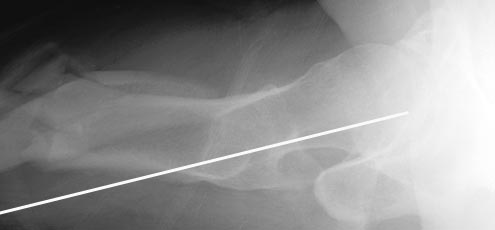

При многооскольчатых переломах стержень может "выпасть" кзади под весом кондуктора и своим, даже если поначалу он вводился правильно. Чтобы эту неприятность предупредить, стоит ввести спицу по оси шейки бедра вдоль ее задней стенки, типа как на картинке. Если стержень кпереди от этой спицы вводить, то он за нее не провалится.